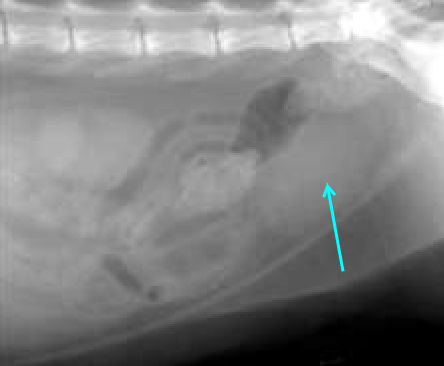

urinary bladder

liver

splenic tail

splenic head

fundus and body

pylorus